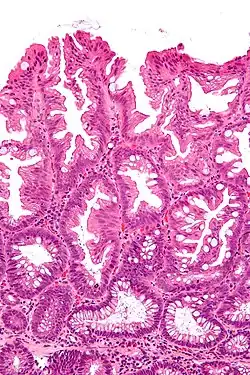

Villous adenoma

Micrograph of a colorectal villous adenoma. H&E stain

These adenomas may become malignant (cancerous). Villous adenomas have been demonstrated to contain malignant portions in about 15–25% of cases, approaching 40% in those over 4 cm in diameter.[7] Colonic resection may be required for large lesions. These can also lead to secretory diarrhea with large volume liquid stools with few formed elements. They are commonly described as secreting large amounts of mucus, resulting in hypokalaemia in patients. On endoscopy, a "cauliflower' like mass is described due to villi stretching. Being an adenoma, the mass is covered in columnar epithelial cells.